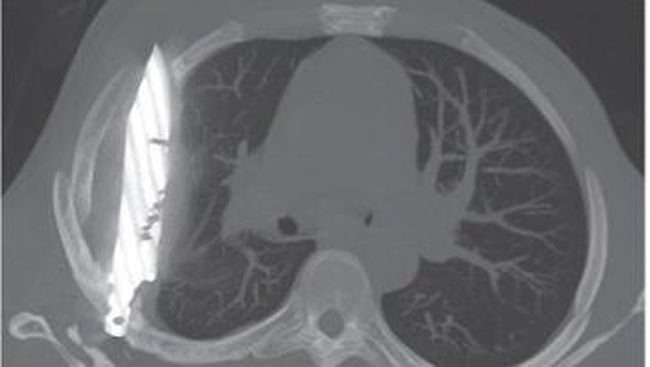

Foto: Journal of Surgical Case Reports

Dokter di Muhimbili National Hospital di Tanzania menemukan sebilah pisau tertanam di dada seorang pria. Pisau itu tidak terdeteksi selama 8 tahun.

Pria itu pergi ke rumah sakit mengeluhkan nyeri dan keluarnya nanah di dekat area putingnya. Dokter terkejut setelah melakukan rontgen ke pria berusia 44 tahun itu, ternyata ada pisau di dalam dada pria itu.

"Rontgen dada lateral awal menunjukkan adanya benda logam tersangkut di bagian tengah dada, dengan bayangan samar di sekitarnya yang mengindikasikan hematoma terlokalisasi kronis yang mengeluarkan cairan, atau fibrosis pascatrauma, kemungkinan besar akibat luka tusukan pisau pasien," tulis dokter dalam jurnal, dikutip detikHealth dari News18, Selasa (19/8/2025).